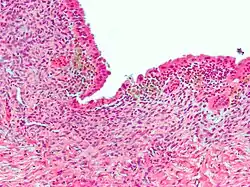

Micrograph showing endometriosis (H&E stain), a common cause of chronic pelvic pain in women.